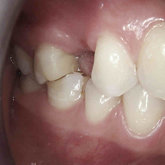

He received his Diploma in Implantology in 2016 from the University of Pretoria, which he passed with Distinction. He is also a member of the International Team for Implantology (ITI), which is based in Switzerland and offers members access to the latest research and cutting-edge techniques.

Porcelain crowns and restorations made in one appointment.

We make it a priority to incorporate the latest in dental technology in everything we do at our practice. ...